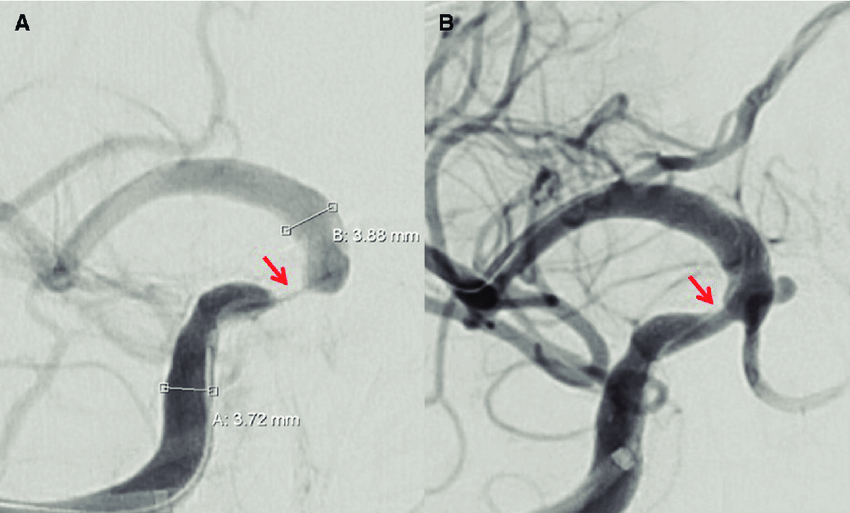

Tratamiento médico vs stent en la estenosis arterial intracraneal grave y sintomática

11 agosto 2022